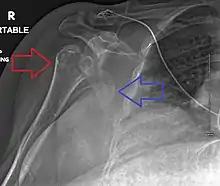

Multi-fragmented, or comminuted fracture of the proximal humerus with involvement of the greater tuberosity

Proximal humerus fracture

Fracture dislocation of the right shoulder